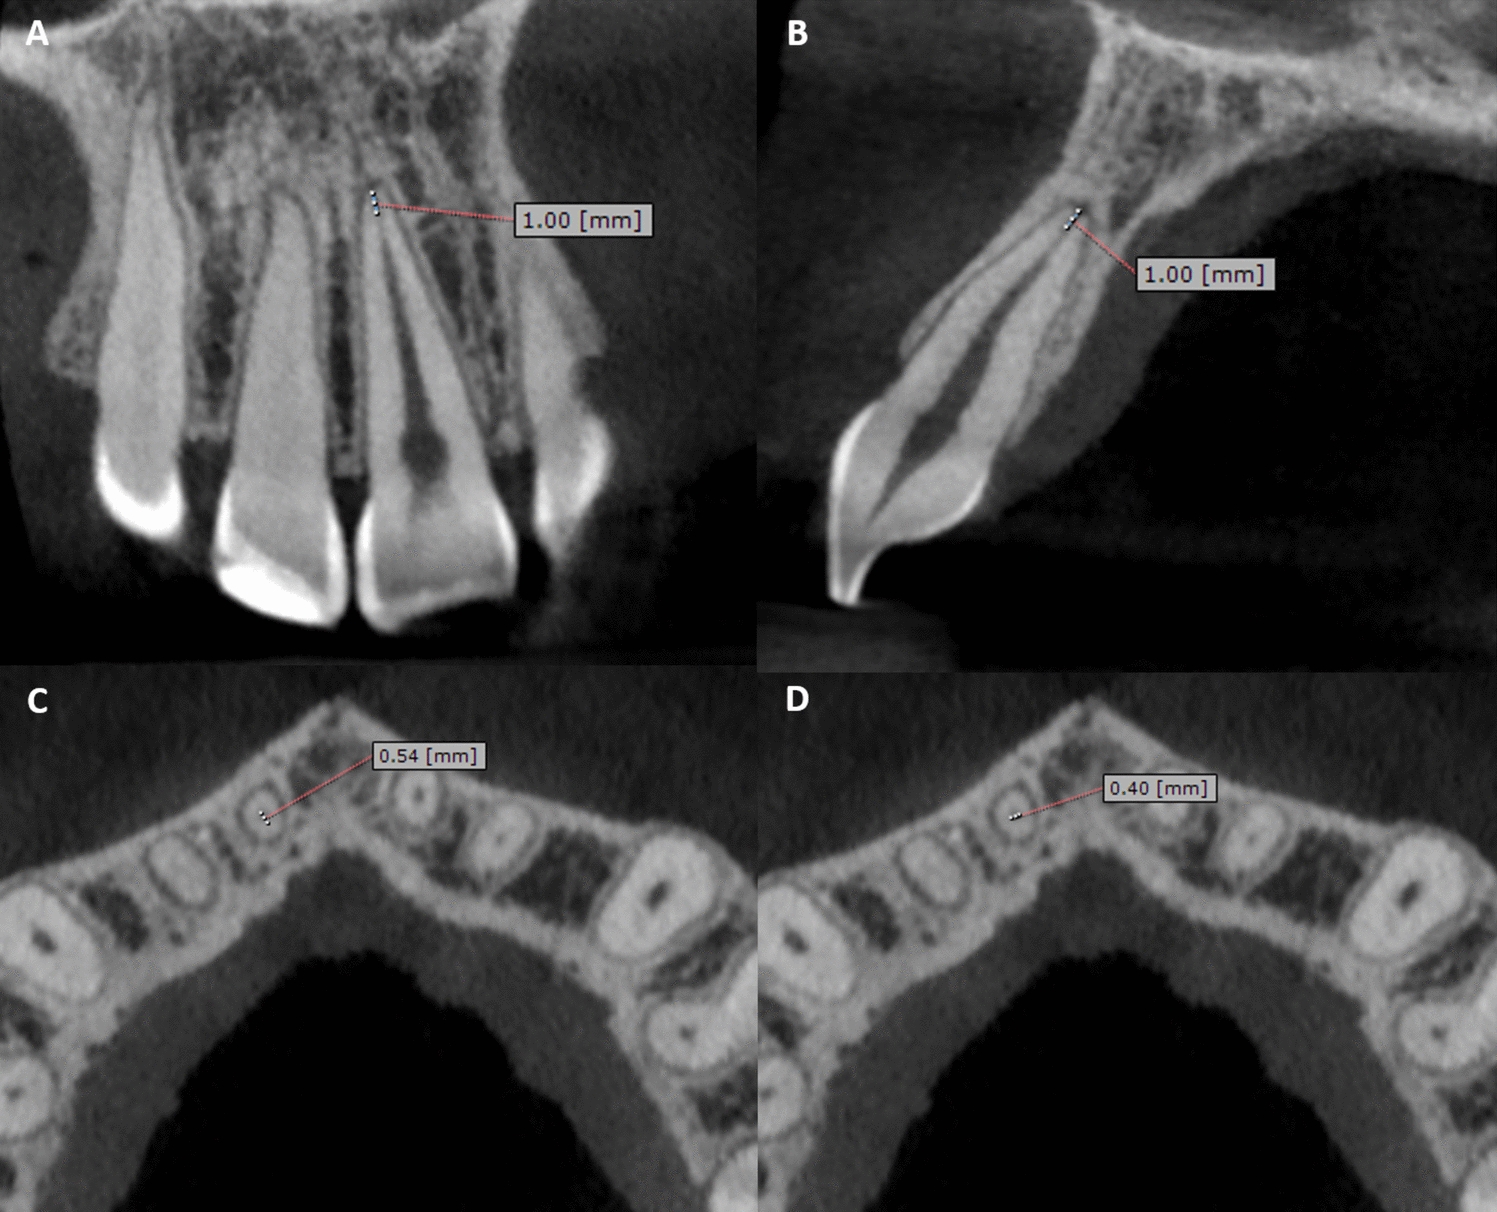

Gulec M, Tassoker M, Ozcan S, Orhan K. Evaluation of the mandibular trabecular bone in patients with bruxism using fractal analysis. Oral Radiol. 2021;37(1):36–45. https://doi.org/10.1007/s11282-020-00422-5.

Kato CN, Barra SG, Tavares NP, Amaral TM, Brasileiro CB, Mesquita RA, et al. Use of fractal analysis in dental images: a systematic review. Dentomaxillofac Radiol. 2020;49(2):20180457. https://doi.org/10.1259/dmfr.20180457.

Citir M, Karslioglu H, Uzun C. Evaluation of mandibular trabecular and cortical bone by fractal analysis and radiomorphometric indices in bruxist and non-bruxist patients. BMC Oral Health. 2023;23(1):522. https://doi.org/10.1186/s12903-023-03245-y.

Valletta A, Tavakoli Tafti K, Baghaei K, Moaddabi A, Soltani P, Spagnuolo G, et al. Evaluating the mandibular trabecular structure in patients with and without bruxism: a cross-sectional study. Appl Sci. 2023. https://doi.org/10.3390/app13074568.